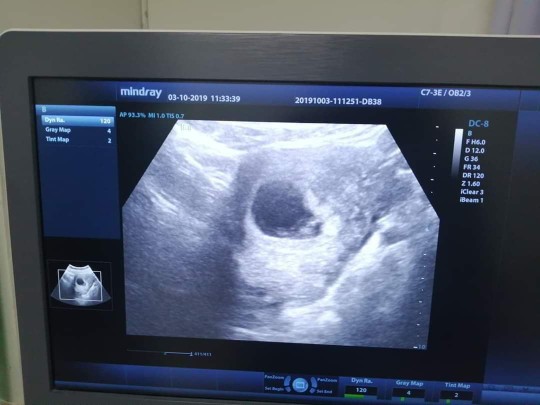

6w2d ค่ะ